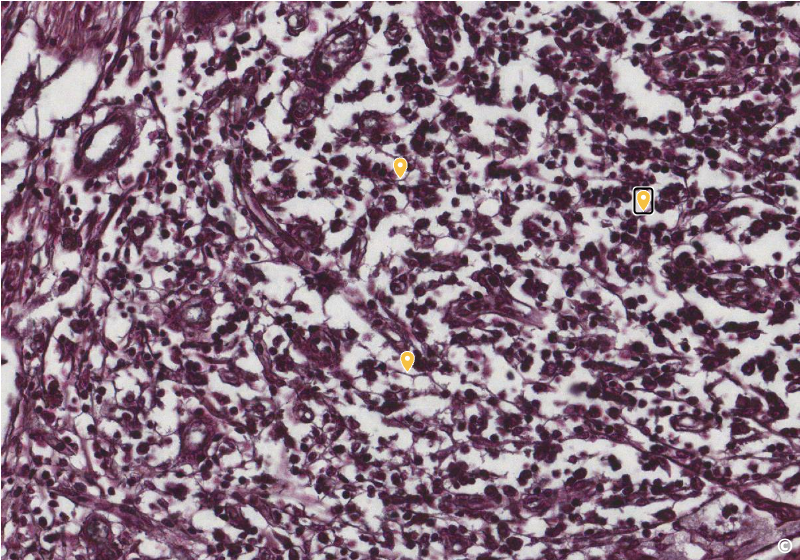

<p>identify area of histological slide, type of CT, and identify structures</p>

identify area of histological slide, type of CT, and identify structures

spleen, reticular fiber, reticulocytes (dark ovals)/reticular fibers